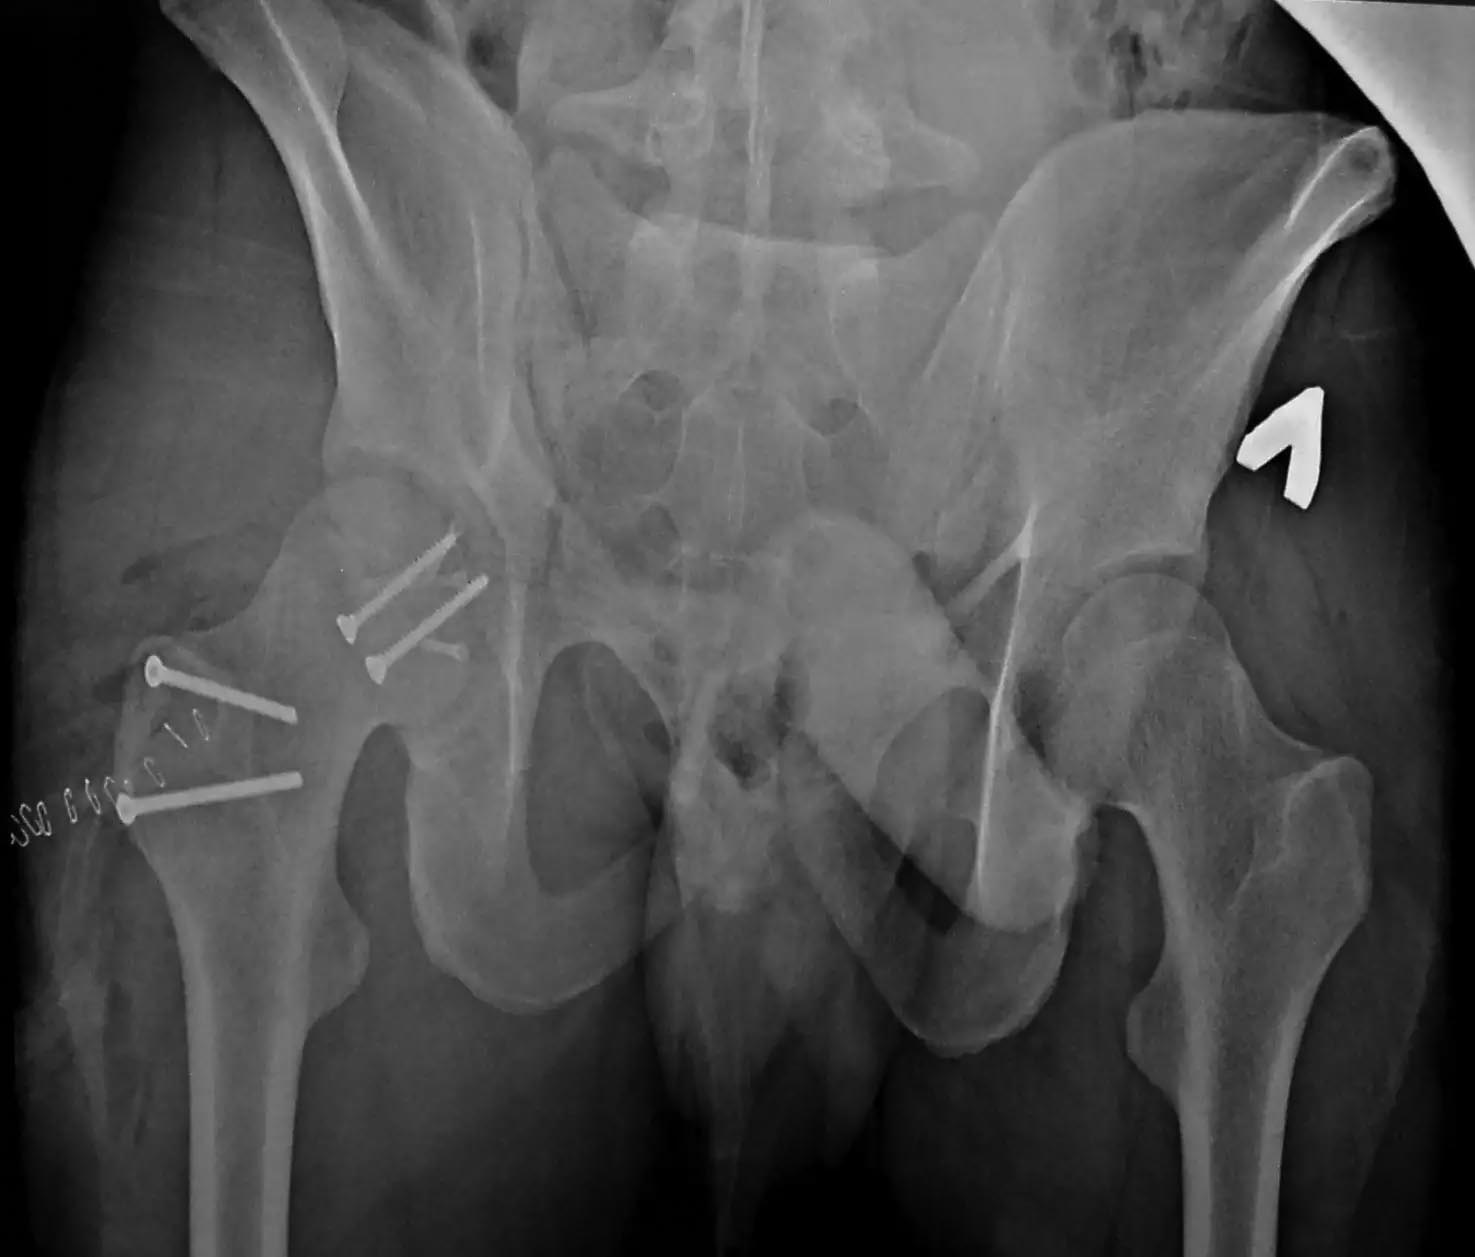

Случай практически идентичный описанный в январе 2015 на ортофоруме Никитой Николаевичем Заднепровским. Молодой человек 20 лет ДТП 23.02.2015, Диагноз: Сочетанная травма. Закрытый переломо-вывих головки и перелом заднего края вертлужной впадины (Pipkin4) правой бедренной кости. Открытый подтаранный вывих правой стопы. При поступлении в ЦРБ вправление вывиха головки бедра и подтаранного вывиха стопы.

Далее перевод к нам в Травмоцентр и 03.03.2015. через 8 дней операция, выполнен остеосинтез головки 3-мя самокомпрессирующими винтами Autofix под разными углами с погружением в субхондральный слой. Доступ Kocher-Langenbeck с флип-остеотомией большого вертела и задним хирургическим вывихом головки бедра. В полости сустава два свободно-лежачих фрагмента хряща головки, которые были удалены. На снимках виден дефект хряща головки после репозиции. Небольшой фрагмент заднего края фиксирован двумя спонгиозными винтами. Далее шов раны с дренированием. На 2 сутки пациент поворачивался на здоровый бок с валиком между ног, на 4 сутки сидел в кровати и на 6 сутки ходил с помощью костылей.